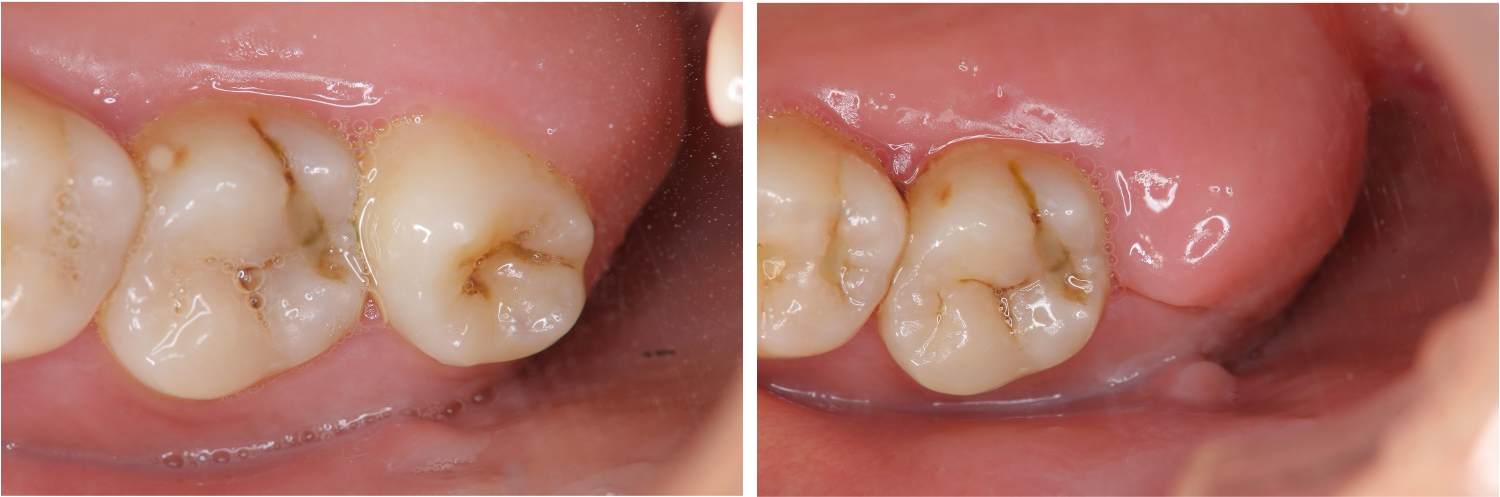

拔牙後傷口處理-牙齦腫-#38

口腔外科

拔牙後傷口處理